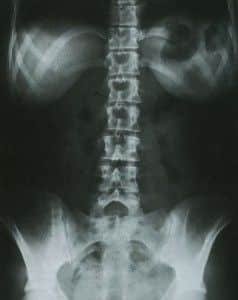

Proyección AP

Paciente en decúbito supino o en bipedestación. Con frecuencia a la proyección AP en decúbito se le denomina abdomen simple y a la AP en bipedestación, abdomen en bipedestación. Para una exploración inicial se debe realizar la AP en

decúbito supino.

Estructuras visibles y criterios de evaluación

El interés de estas proyecciones es el estudio de las diferentes estructuras óseas y viscerales del abdomen, la búsqueda de cálculos opacos y otras calcificaciones, la localización de masas abdominales y la apreciación de anomalías de tamaño o forma de los órganos macizos (riñones, hígado, bazo) o huecos (estómago, vesícula, colon…)

− Se incluirá desde el abdomen superior hasta la sínfisis del pubis

− El paciente estará alineado: columna vertebral en el centro de la radiografía, costillas, pelvis y caderas equidistantes de los bordes de la placa

− No existirá rotación: apófisis espinosas en la línea media de las vértebras lumbares, huesos ilíacos simétricos

− Densidad adecuada de tejidos blandos que permita apreciar: pared abdominal lateral, psoas, borde inferior del hígado y riñones.